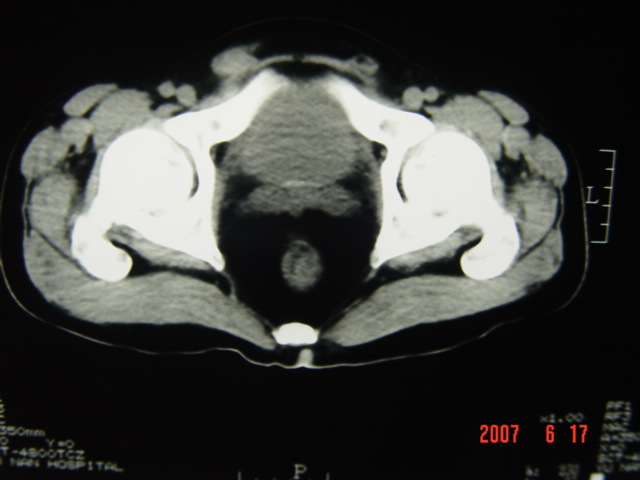

[br][br]以下是引用lkc8963在2007-6-17 13:32:00的发言:[br]完全支持邓主任意见:降/乙交界部占位性病变伴不全梗阻.做个增强或者be可能更好.